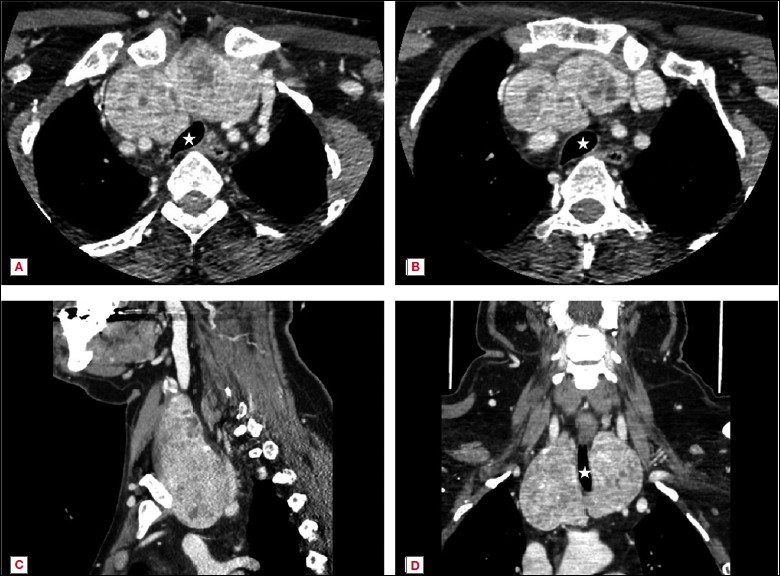

Objective: Intrathoracic goiters (ITGs) pose numerous challenges to head and neck surgeons due to the intricate relationships with major vessels and other mediastinal structures. Surgical excision remains the mainstay of treatment and we herein present an update on this topic.

Results: Transcervical excision is the commonest approach for treating ITGs, yet the potential need for a transthoracic approach must be always kept in mind. An acceptable rate of postoperative complications is expected if surgeries are carried out by experienced and dedicated surgical teams.